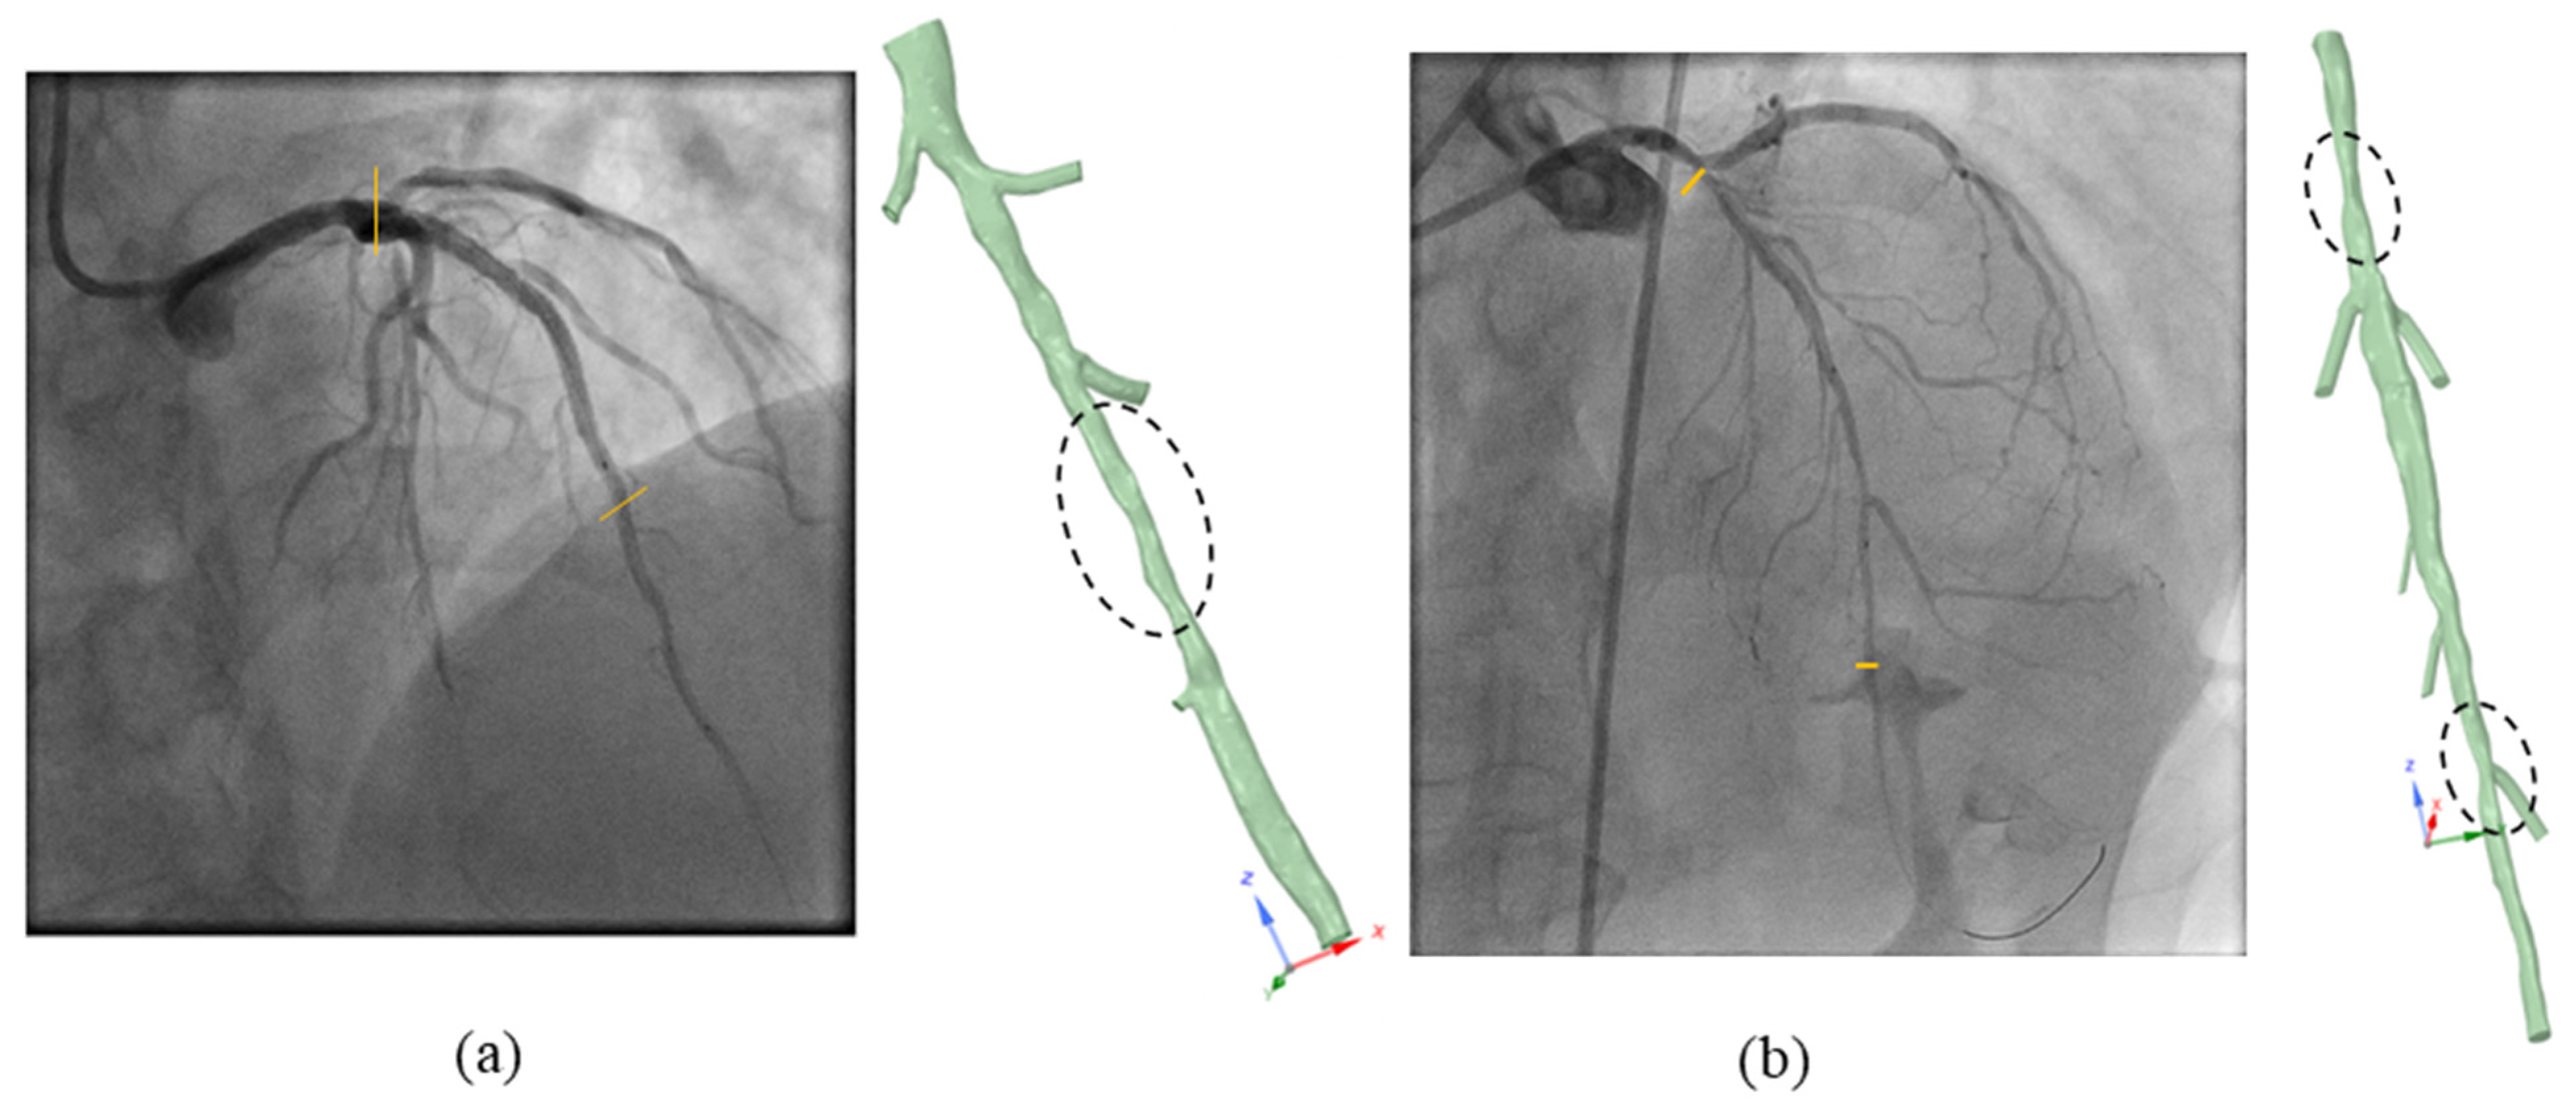

2.3. Clinical FFR Measurement

3.2. FFR Analysis in OCT-Reconstructed Vessel Models

3.3. Implications on FFR Computation Using OCT Imaging